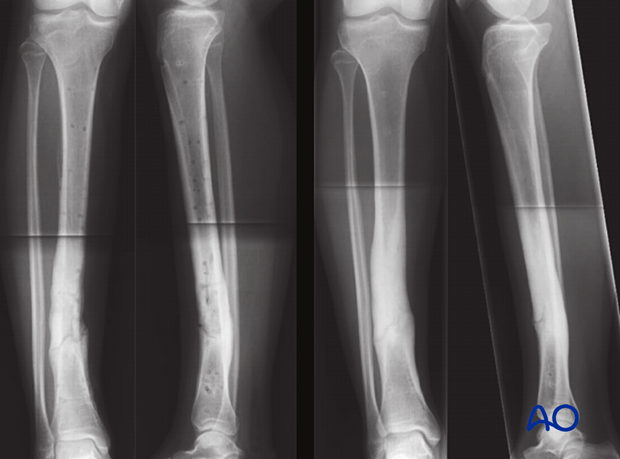

Six weeks after placement of the ring fixator good healing was observed, and the ring fixator was removed (image on left). Radiological control after one year shows good fracture healing (image on right).